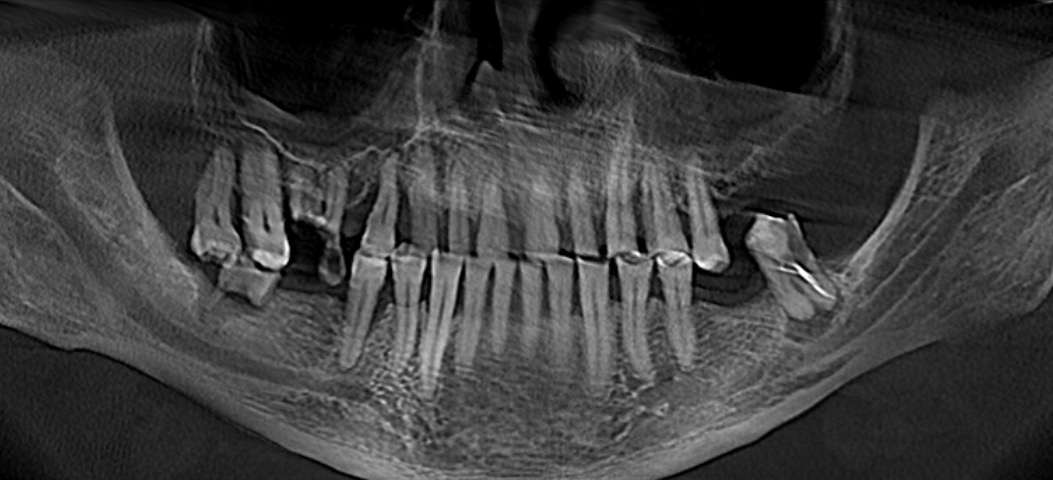

Я подготовился к приему заранее, посмотрел компьютерную томографию, которую он мне прислал.

По снимку видно, что необходим комплексный подход к проблеме, который будет включать в себя мою работу как хирурга, так и смежных специалистов. Гигиениста, стоматолога-протезиста и стоматолога-терапевта.